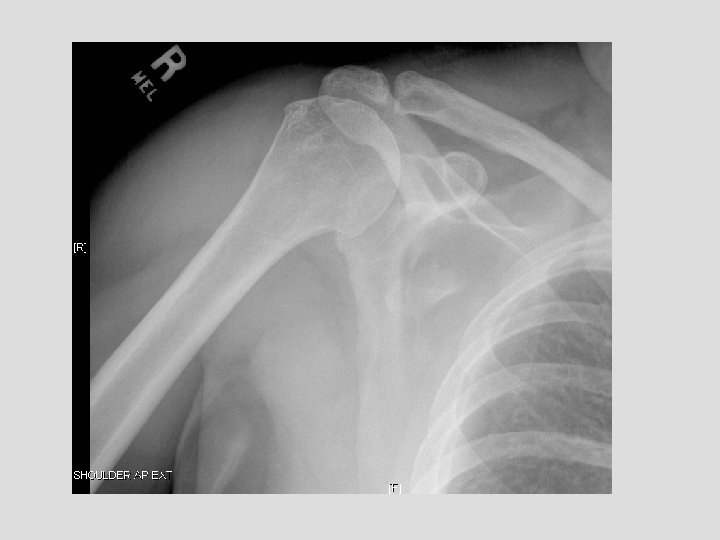

Findings and Differentials Findings: On the CXR, there is a piece of bone overlying

Findings and Differentials Findings: On the CXR, there is a piece of bone overlying the right scapula, which could easily be missed. The follow-up shoulder series and CT more clearly demonstrate a fracture. The CT clearly shows the donor site to be the coracoid process. Differentials: • Coracoid avulsion fracture